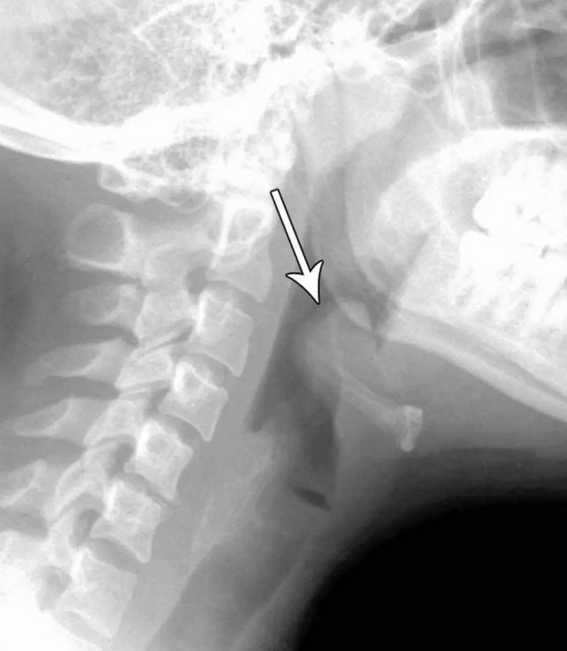

Studying Medicine on Twitter "Acute epiglottitis epiglottis